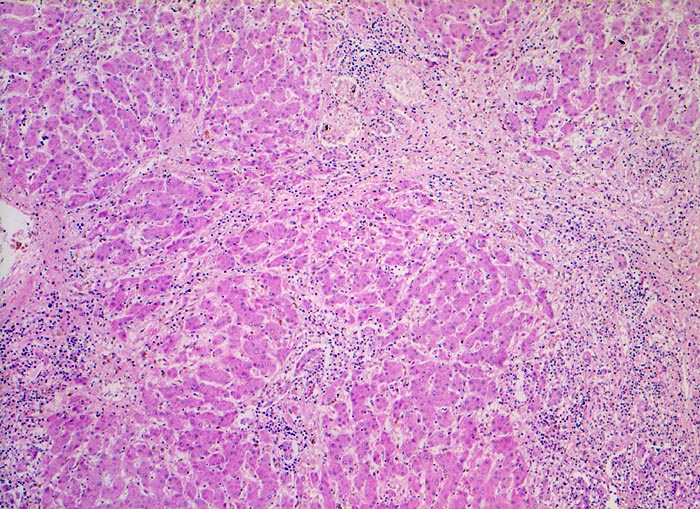

Das histologische Bild der akuten Hepatitis vom Virustyp ist gekennzeichnet durch eine lobuläre Entzündung bei fehlender portaler Fibrose und nur geringer entzündlicher Infiltration der Portalfelder. Es finden sich ballonierte Hepatozyten, Apoptosen ( 1164) und fleckige Nekrosen. Perivenuläre Nekrosen, Brückennekrosen oder konfluierende multilobuläre Nekrosen und eine läppchenzentrale Cholestase können vor allem in klinisch fulminant verlaufenden Fällen nachgewiesen werden. Zahlreiche Makrophagen, welche Diastase-PAS positives Zeroidpigment ( 4319) von phagozytierten nekrotischen Hepatozyten enthalten, zeugen im subakuten Stadium von einer abgelaufenen akuten Hepatitis mit Parenchymnekrosen. Eine Unterscheidung der verschiedenen Typen der viralen Hepatitis und einiger Formen medikamentöser Hepatitiden gelingt rein morphologisch aufgrund des unspezifischen Bildes meist nicht. Für eine ätiologische Klassifizierung sind zusätzliche klinische Angaben erforderlich (Anamnese, Medikamente, Serologie).